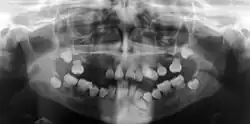

Die Dentindysplasie (DD) ist eine seltene angeborene Störung der Dentinbildung. Bei dieser Zahnentwicklungsstörung sieht das Dentin der Zahnkronen normal aus, die Zahnpulpa ist verödet, die Zahnwurzeln sind nicht normal ausgebildet. Es besteht eine Neigung zu knöchernen Veränderungen der Alveolarknochen.[1]

Die Diagnose ergibt sich aus der zahnärztlichen Untersuchung einschließlich der Orthopantomographie.[10]